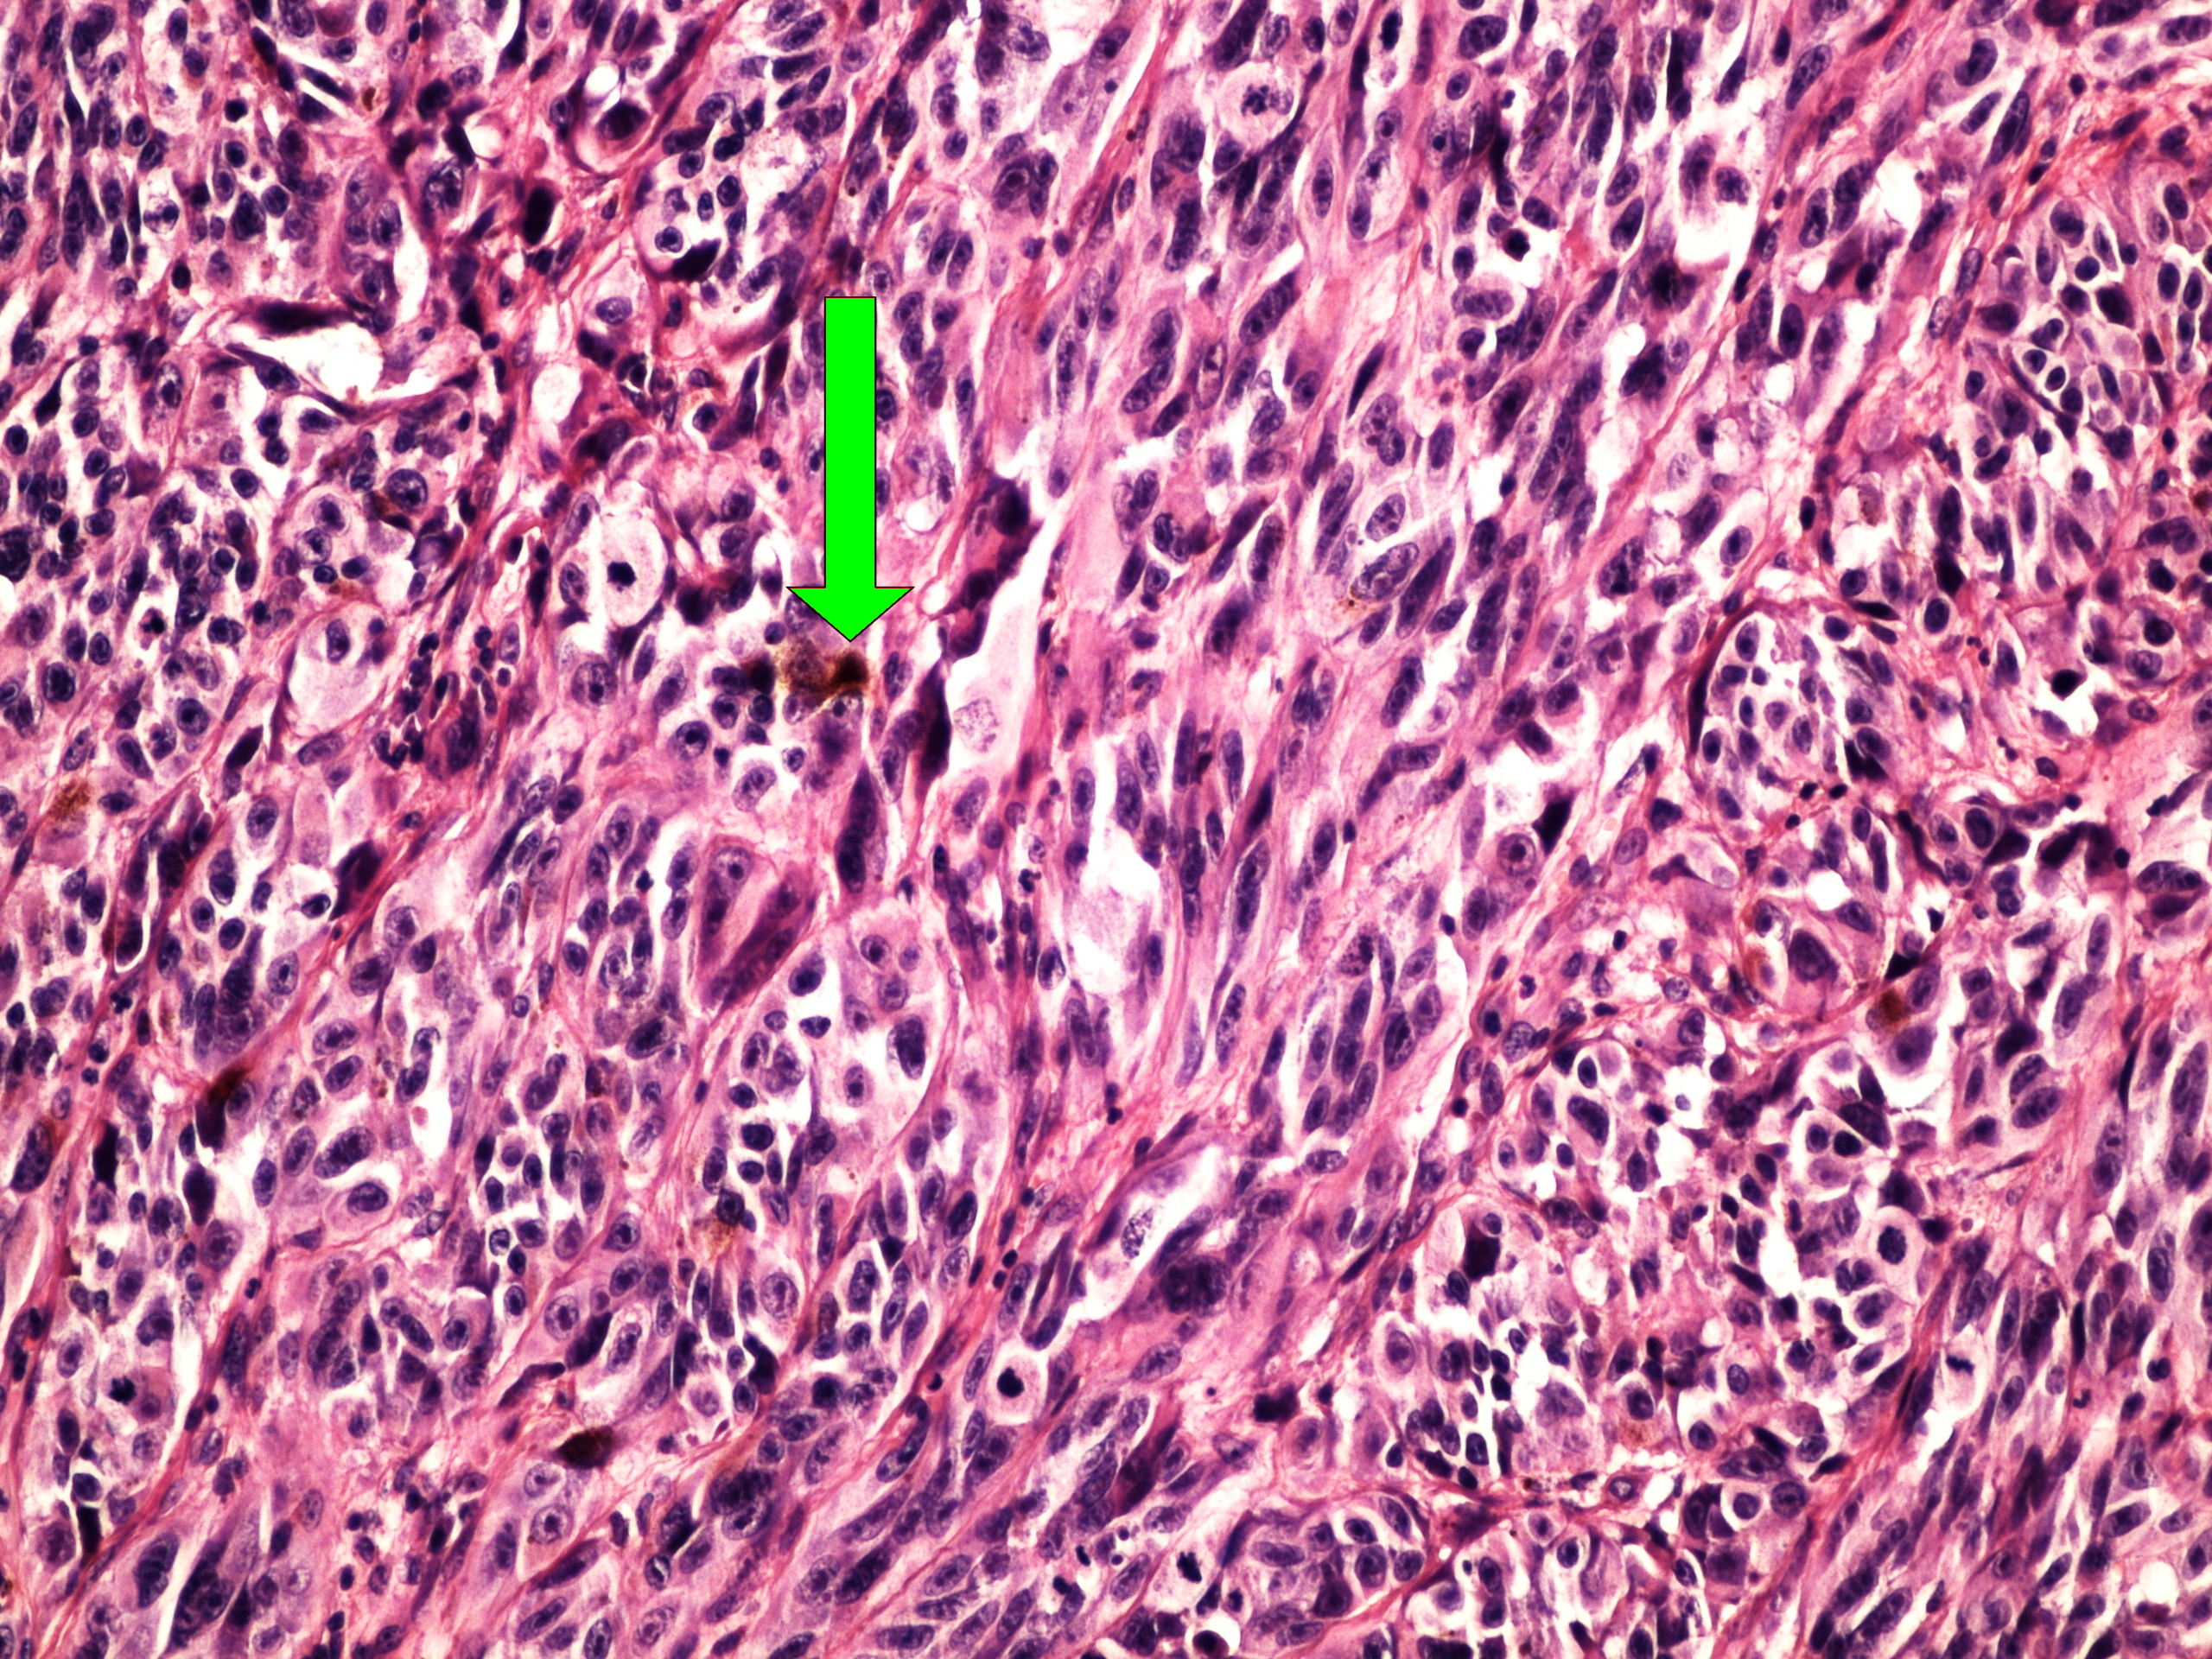

Preparát č.17 a č.18 – melanom

Struktury

- hnědá pigmentace - melanin